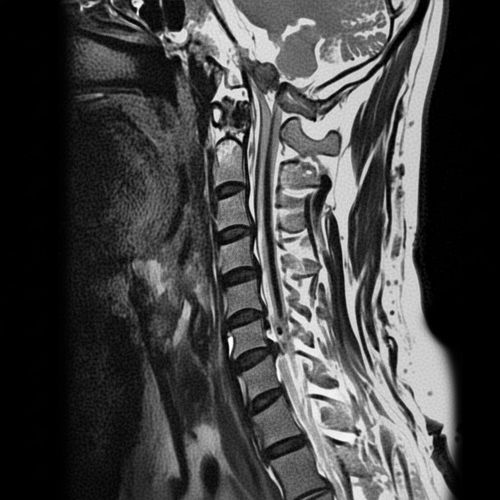

경추협착증은 경추(목 , 척추)의 척추관이 좁아져서

척추 신경이나 척수에 압박이 가해지는 상태를 말합니다.

경추(목뼈) 부의 척추관 협착증을 일컫는 말로

척추관이 좁아져 팔이나 다리로 가는 신경을 압박함으로써 증상이 나타나는 질환